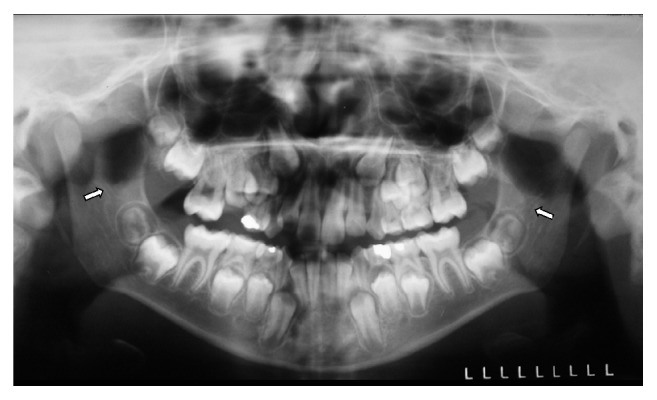

背景。后磨牙管(RMC)是一种解剖变异,可引起牙科手术并发症。方法。根据年龄、性别、两侧下颌副管和下颌副孔的存在情况对500张全景x线片进行RMC评估,这些x线片属于7至20岁的个体。通过Fisher精确检验和Pearson卡方检验研究感兴趣的相关性,通过Pearson相关系数(r)研究相关性,使用显著性水平为5%。结果。44张x线片(8.8%)观察到RMC,其中24位为女性。RMC与年龄无统计学意义(p > 0.05);Fisher精确检验)、性别(p = 0.787;Pearson's Chi-Square检验)、两侧下颌管和颏孔数量(p > 0.05;皮尔逊卡方检验)。RMC与侧位有显著相关性,右侧根管频率较高(p < 0.05;费雪精确检验)。结论。尽管RMC的发生率很低,但其识别和确认其尺寸和路径是相关的,主要是在麻醉和外科手术可能出现失败或困难的情况下。

Background. The retromolar canal (RMC) is an anatomical variation that can cause complications in dental procedures. Method. The RMC was evaluated according to age, sex, and presence of accessory mandibular canal and accessory mental foramen, on both sides in 500 panoramic radiographs, belonging to individuals at the age of 7 to 20 years. The associations of interest were studied through Fisher's Exact Test and Pearson's Chi-Square Test, and the correlation was studied through Pearson's Correlation Coefficient (r). The significance level used was 5%. Results. The RMC was observed in 44 radiographs (8.8%), and out of those 24 were females. There was no statistically significant association between the RMC and age (p > 0.05; Fisher's Exact Test), sex (p = 0.787; Pearson's Chi-Square Test), amount of mandibular canals and mental foramina, on both sides (p > 0.05; Pearson's Chi-Square Test). There was a significant association between RMC and side, the higher frequency of the canal being on the right side (p < 0.05; Fisher's Exact Test). Conclusions. Despite the low occurrence of the RMC, its identification and the verification of its dimensions and path are relevant, mainly in cases when anesthetic and surgical procedures can present failures or difficulties.